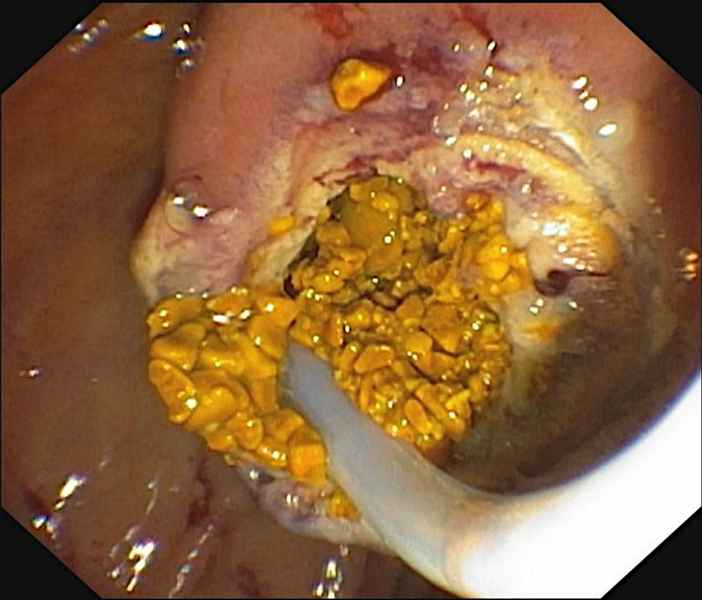

Endoscopic marsupialization of duodenal duplication cysts